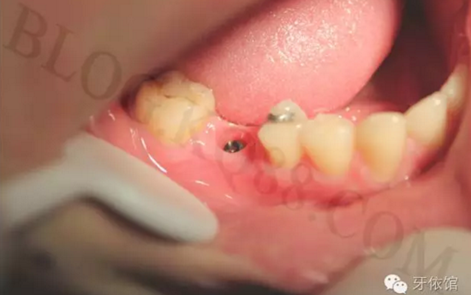

術(shù)后三個月的口內(nèi)照片。

卸下愈合基臺,可見袖口干凈整潔。